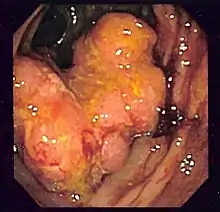

| نمایی از مجموعه گوارشی بخش پایینی (لوله گوارشی تحتانی) | |